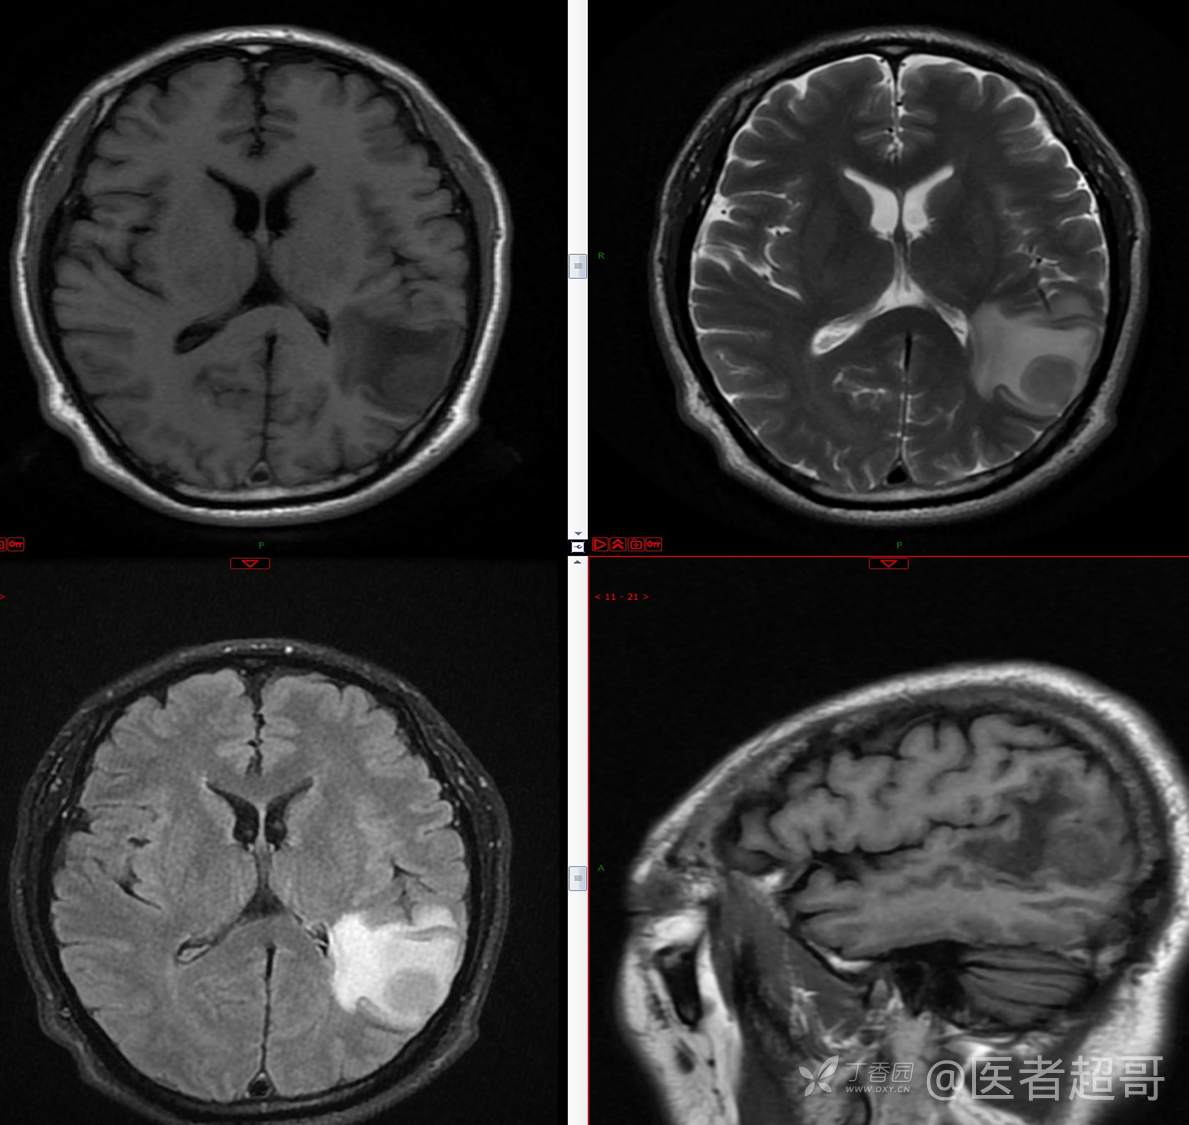

比较典型病例,CT、MRI齐全,请分析,领丁当!

男,56岁

主 诉:查体发现颅内占位10天。

现病史:患者于约10天前于我院查体时行颅脑MRI提示左侧顶叶占位病变,无头痛头晕,无恶心呕杜,无肢体活动不利,无感觉异常,现患者为求进一步治疗,就诊于我科门诊,门诊以“颅内占位性病变”收入我科。患者自发病以来,神志清,精神可,饮食及睡眠差,大小便无明显异常,体重无明显变化。